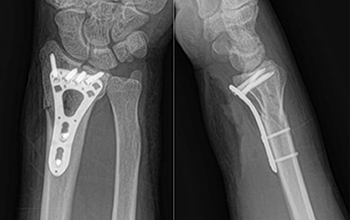

At CZMEDITECH, we are dedicated to providing reliable orthopedic solutions through real clinical success. Each surgical case reflects our continuous innovation in spinal fixation, trauma management, joint reconstruction, maxillofacial repair, and veterinary orthopedics. By integrating advanced manufacturing technology with the expertise of experienced surgeons, we ensure every implant delivers safety, precision, and long-term recovery.

Explore below a selection of clinical cases that demonstrate how our CE-certified implants help restore mobility, stability, and confidence in patients worldwide.